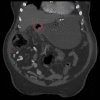

Every trick in the book: EUS angiotherapy for management of refractory bleeding secondary to a complicated duodenal ulcer in a patient with Roux-en-Y gastric bypass